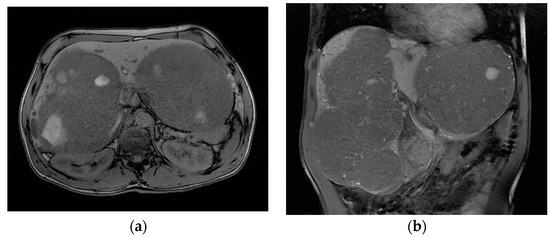

The patient was referred to our tertiary hepato-bilio-pancreatic surgery center to reassess GLM resectability. At this point, the patient was handicapped due to the giant metastases impeding walking and breathing; the ECOG performance status was 4, and the Charlson comorbidity index was 6. At imaging, aside from several small metastases in the central part of the liver (liver segments 4, 5, and 8), there were two large groups of confluence metastases: One was 17/10 cm in size, completely occupying segments 6 and 7, partly occupying segments 5 and 8, and invading the right hepatic vein. The other was 14/11 cm in size, occupying the entirety of segment 2, partly occupying segments 3 and 4 superior, and invading the left hepatic vein (Figure 4). Total liver volume was 5092 cm3; left hemiliver volume was 1876 cm3, while right hemiliver volume was 3217 cm3.

Figure 4.

MRI showing the two groups of large liver metastases: (a) one group located in segments 6 and 7 and partly in segments 5 and 8, invading the right hepatic vein, while (b) the other occupied the entirety of segment 2 and partly occupied segments 3 and 4 superior, invading the left hepatic vein.